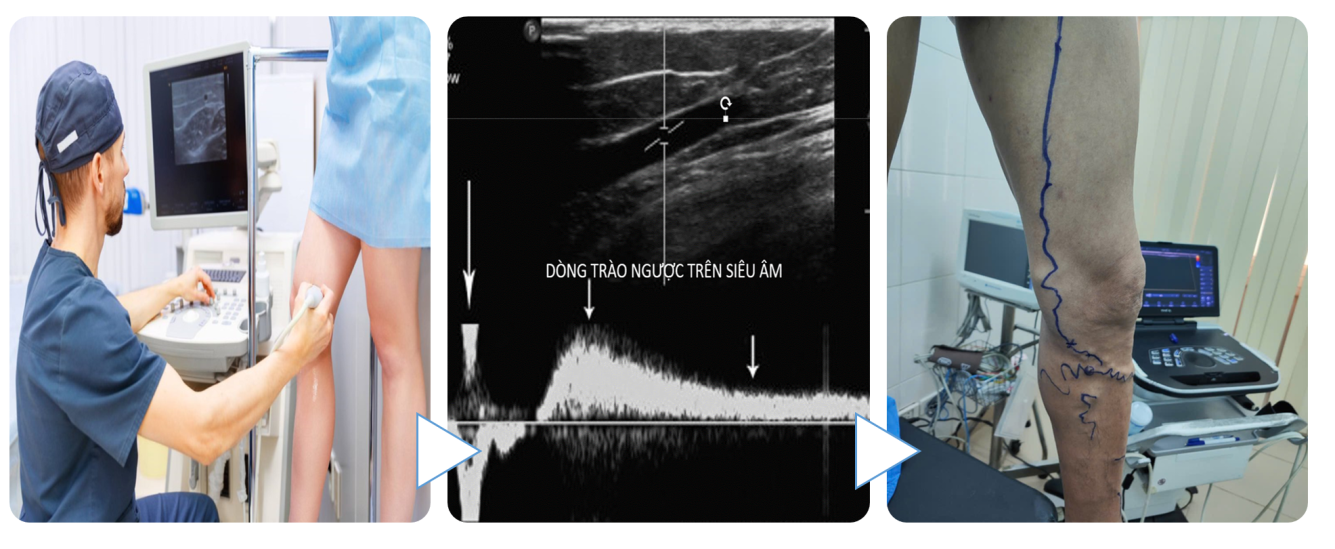

• Siêu âm Doppler mạch máu:

Siêu âm xác định chẩn đoán khi ghi nhận dòng trào ngược qua van tĩnh mạch với thời gian kéo dài >0.5 giây ở tĩnh mạch hiển và tĩnh mạch sâu ở cẳng chân hoặc > 1 giây ở tĩnh mạch đùi khoeo.

Siêu âm còn xác định vị trí tổn thương của tĩnh mạch, đánh giá huyết động của tĩnh mạch, từ đó giúp lập bản đồ tĩnh mạchvà lựa chọn kỹ thuật điều trị phù hợp.

Siêu âm Doppler là phương pháp hiện đại, giúp phát hiện suy tĩnh mạch chi dưới